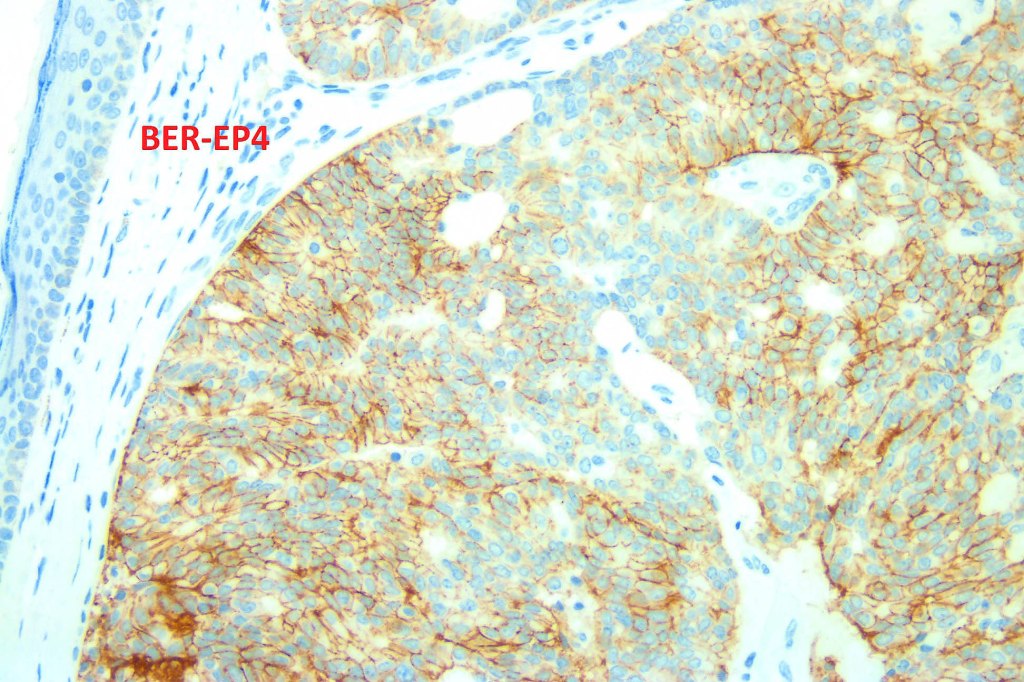

•CAM 5.2, AE1/AE3, CK7, estrogen receptor, progesterone receptor, mammaglobin, GATA3, GCDFP-15, EMA & CEA +ve

. EMPSGCa shares this IHC profile